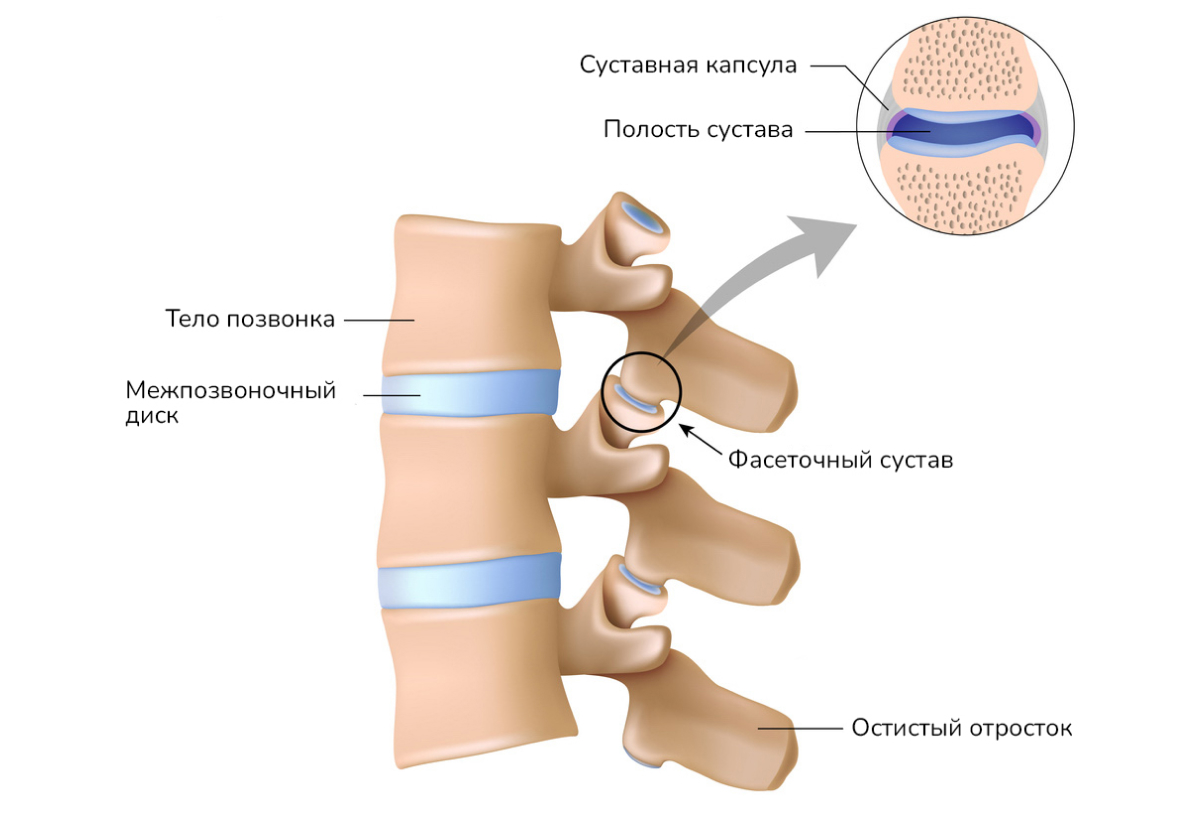

Остеоартрит фасеточных суставов: медицинские снимки и схемы